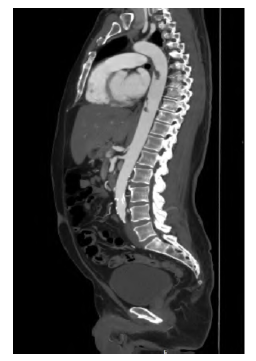

However, one week later, the patient developed symptoms of pain and paresthesia in the left lower limb, without motor impairment. On physical examination, only the right femoral pulse was palpable. An arterial Doppler ultrasound identified emboli in the left femoral arteries. These findings were confirmed by CTA, which revealed near-total occlusion of the left common femoral artery at its bifurcation and a distal occlusion of the left superficial femoral artery. The CTA also identified two distinct pedunculated floating thrombi in the descending thoracic aorta. The proximal thrombus appeared to be the same one previously detected incidentally, though it had decreased in size. The distal thrombus, however, was a new finding, Figure 1. Hence, a diagnosis of left acute limb ischemia, Rutherford grade IIa, due to embolization originating from a PAMT was assumed. Continuous perfusion of unfractionated heparin was initiated, and urgent surgery was proposed.

Two pediculated thrombi are visible in the anterior aspect of the descending thoracic aorta. Two pediculated thrombi are visible in the anterior aspect of the descending thoracic aorta.